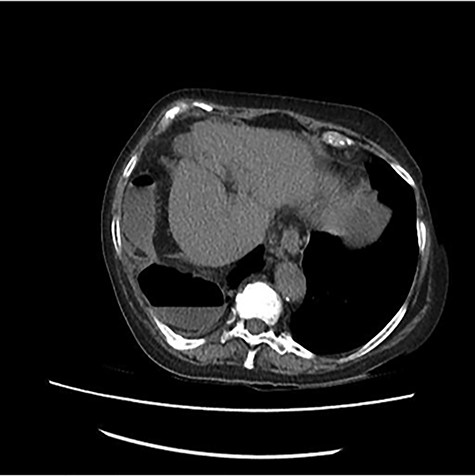

The scanner demonstrated a colonic occlusion resulting from an incarceration, which was diagnosed as a hernia of Bochdalek containing the hepatic angle of the colon (Fig. 2–4).

: CT scan images demonstrating a right diaphragmatic hernia containing intestine.

CT scan images demonstrating a right diaphragmatic hernia containing intestine.